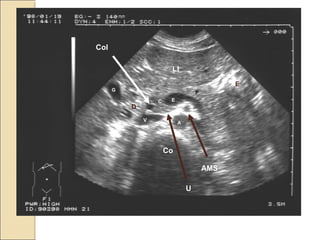

Corte oblícuo-

transversal

subcostal

derecho.

Con o sin apnea

respiratoria

Médida máxima

Porta 12 mm.

Colédoco (Vía

biliar común) 5 –

7 mm.

C

P

E

V

LI

G

A

Co

Col

D

U

AMS

WIRSUNG